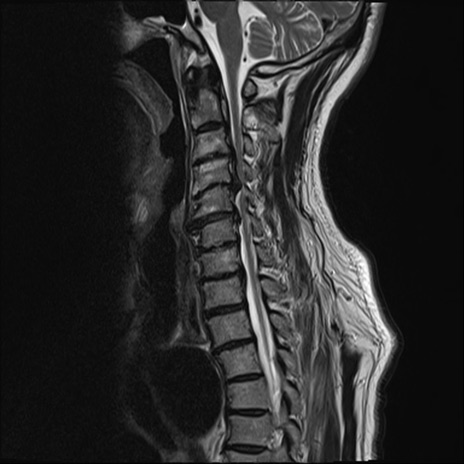

【整形】TIPS症例7 頚椎MRI T2WI(矢状断像)

頚椎MRI

T1WI(矢状断像)